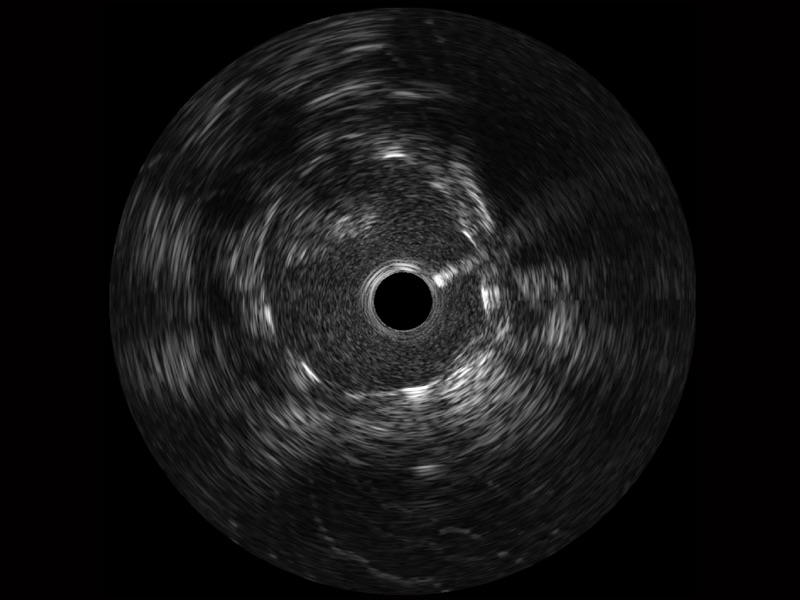

• 银河集团官网宽频IVUS图像

对比传统IVUS导管成像,银河集团官网宽频IVUS图像的近场支架梁显影更细腻,远场中膜外血管仍清晰可辨,兼顾远中近,兼顾分辨力与穿透深度